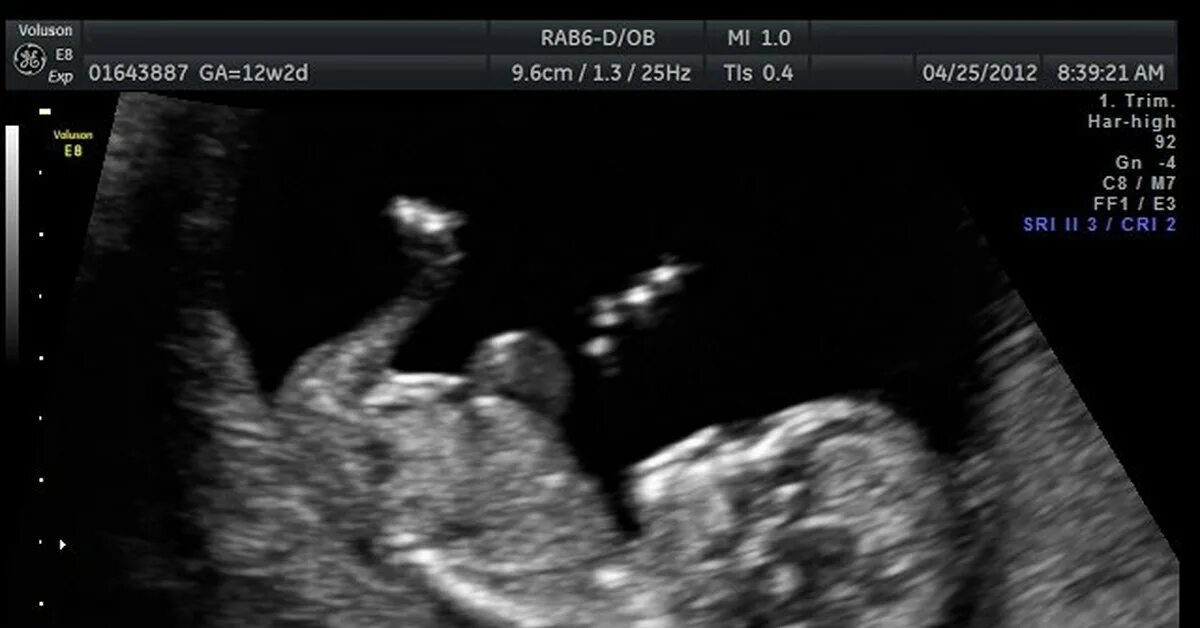

10 неделя пол ребенка